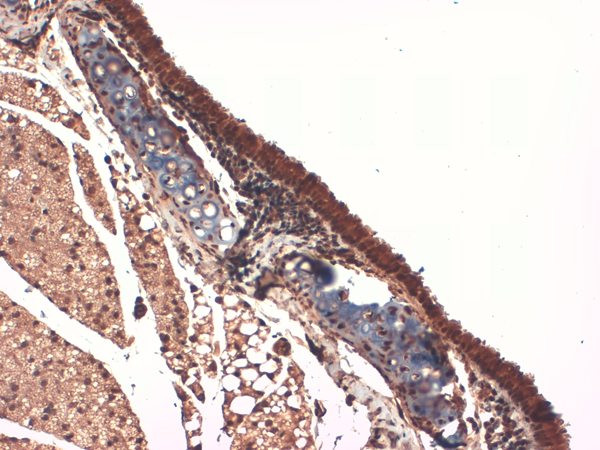

IHC (Immunohistochemistry)

(Immunohistochemistry analysis using Mouse Anti-Sodium Iodide Symporter Monoclonal Antibody, Clone 14F. Tissue: Thyroid. Species: Mouse. Fixation: 10% Formalin Solution for 12-24 hours at RT. Primary Antibody: Mouse Anti-Sodium Iodide Symporter Monoclonal Antibody at 1:1000 for 1 hour at RT. Secondary Antibody: HRP/DAB Detection System: Biotinylated Goat Anti-Mouse, Streptavidin Peroxidase, DAB Chromogen (brown) for 30 minutes at RT. Counterstain: Mayer Hematoxylin (purple/blue) nuclear stain at 250-500 ul for 5 minutes at RT.)